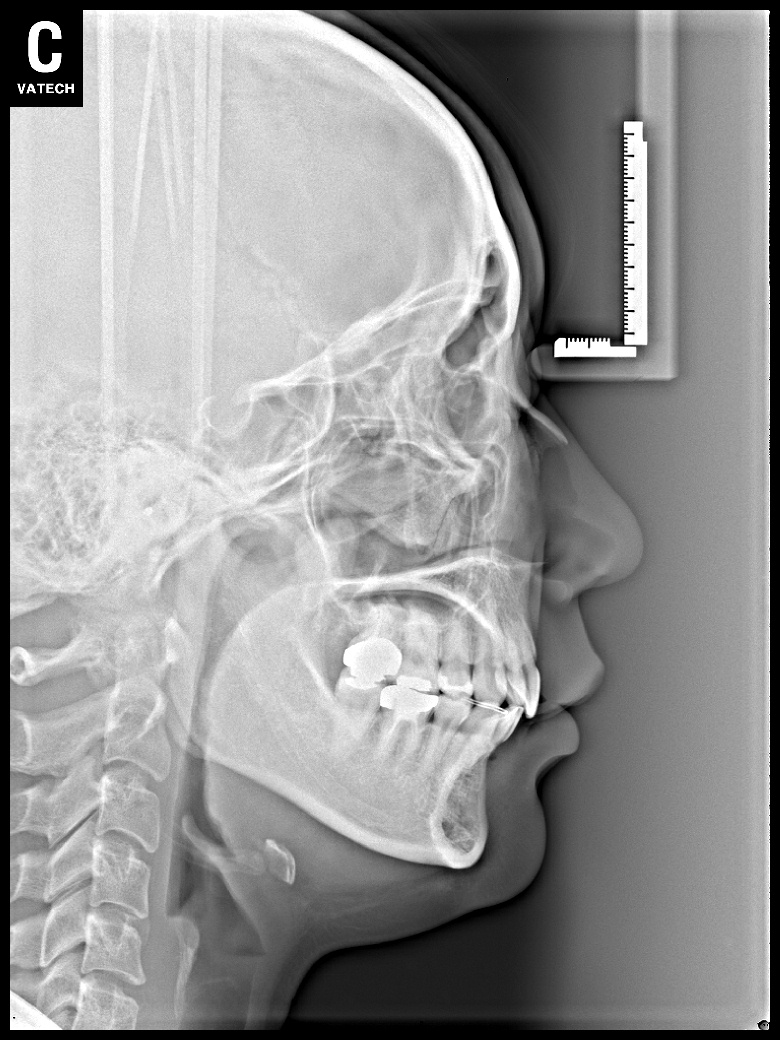

치료 후 사진입니다.